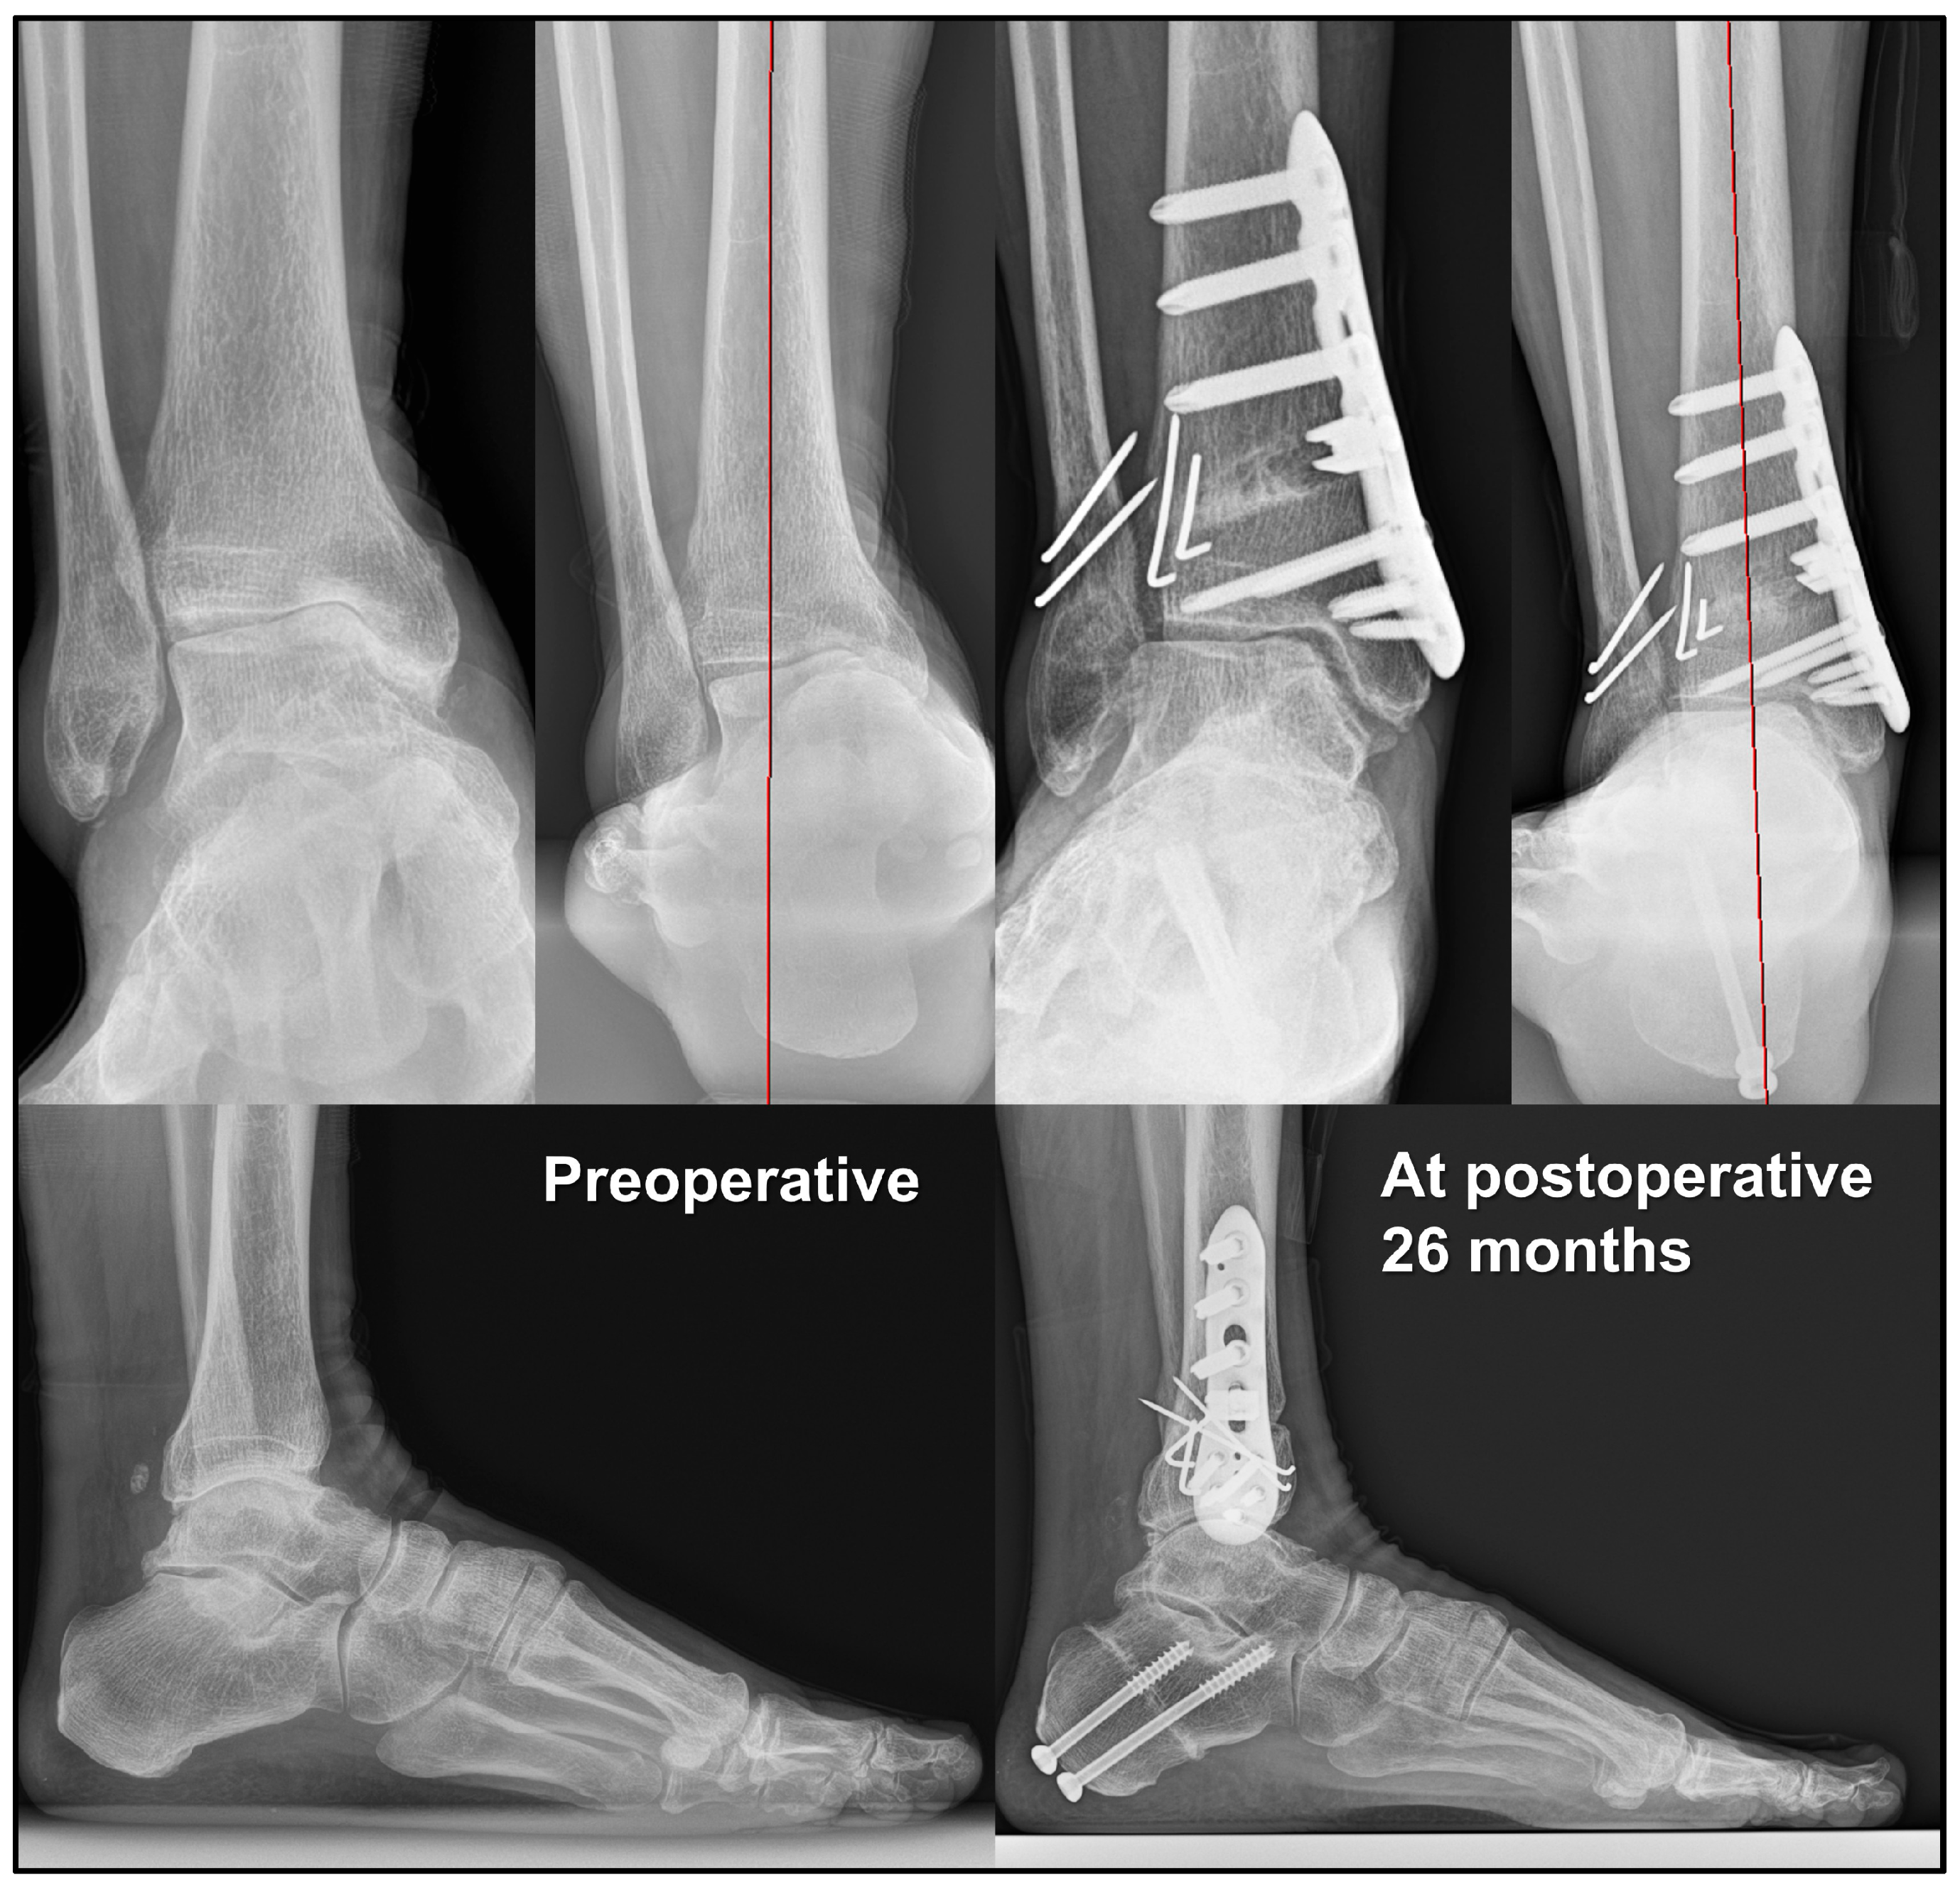

- Choi, J.Y.; Suh, J.S. Joint preserving procedures for Takakura stage IIIB varus ankle osteoarthritis. BMJ Case Rep. 2024, 17, e260585. [Google Scholar] [CrossRef]

- Park, C.H.; Kim, J.B.; Kim, J.; Yi, Y.; Lee, W.C. Joint preservation surgery for varus ankle arthritis with large talar tilt. Foot Ankle Int. 2021, 42, 1554–1564. [Google Scholar] [CrossRef]